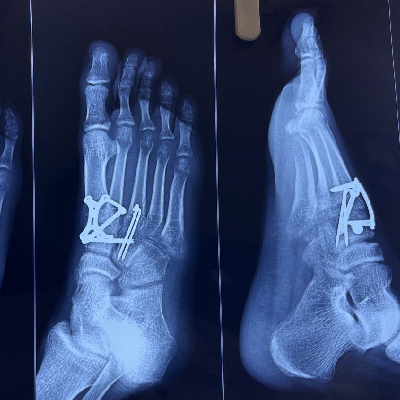

Cavus Foot की सर्जरी के बाद, मरीज अब आराम से चल पा रहा है।

Equino-Cavo-Varus is a complex foot deformity involving high arches, inward heel turning, and toe pointing. Treatment often includes surgery, bracing, or physiotherapy to restore proper alignment and function.